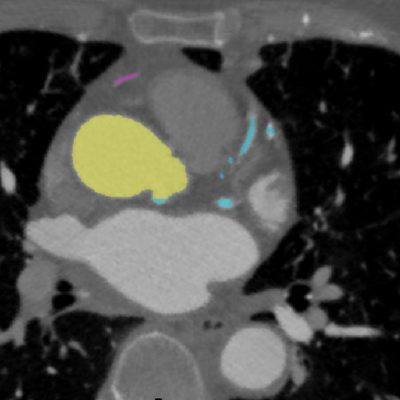

Segmentation of medical images is a way to mark/label anatomical structures: lesions or other relevant objects on medical images. The markings of relevant structures are called masks or labels.

An example segmentation of the aorta and coronary arteries in 2D and 3D

Figure 3: Masks of aorta and coronary arteries on CTA image. [source: image is from the collection of Rotterdam Coronary Artery Algorithm Evaluation Framework, http://coronary.bigr.nl; H.A. Kirişli, M. Schaap, C. Metz, A.S. Dharampal, W.B. Meijboom, S.L. Papadopoulou, A. Dedic, K. Nieman, M.A. de Graaf, M.F.L. Meijs, M.J. Cramer, A. Broersen, S. Cetin, A. Eslami, L. Flórez-Valencia, K.L. Lor, B. Matuszewski, I. Melki, B. Mohr, I. Öksüz, R. Shahzad, C. Wang, P.H. Kitslaar, G. Unal, A. Katouzian, M. Orkisz, C.M. Chen, F. Precioso, L. Najman, S. Masood, D. Ünay, L. van Vliet, R. Moreno, R. Goldenberg, E. Vuçini, G.P. Krestin, W.J. Niessen, T. van Walsum,”Standardized evaluation framework for evaluating coronary artery stenosis detection, stenosis quantification and lumen segmentation algorithms in computed tomography angiography”, Medical Image Analysis, 17(8), 859–876 (2013)].